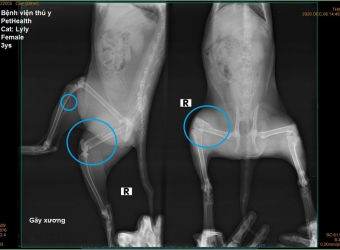

X-quang chấn thương, gãy xương chó mèo tại Sing Pet Biên Hòa, Đồng Nai. Chẩn đoán nhanh, chính xác, an toàn, hỗ trợ điều trị gãy xương, trật khớp và hồi phục hiệu quả.